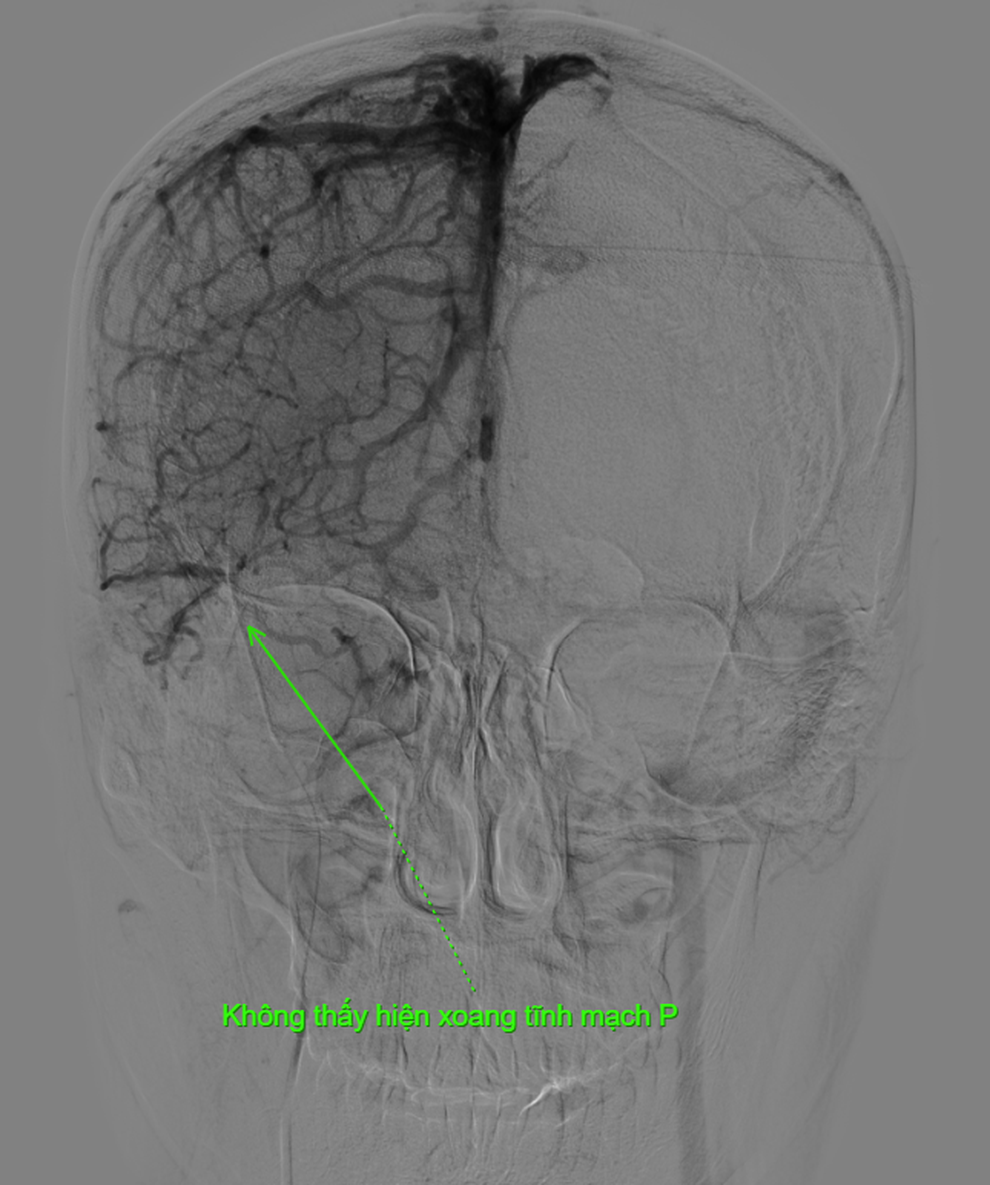

Vài ngày sau tai nạn, anh S.T. (35 tuổi) bất ngờ chảy máu vết thương trở lại, đau đầu dữ dội và rối loạn hành vi.Nhận thấy tình trạng nghiêm trọng, gia đình quyết định vượt hàng trăm cây số, đưa nam thanh niên đến Bệnh viện Nam Sài Gòn (TPHCM), vì biết nơi này có khoa Ngoại Thần kinh - Cột sống chuyên điều trị các ca chấn thương sọ não phức tạp.Tại đây, kết quả chụp CT cho thấy bệnh nhân bị lún sọ trán hai bên, dập xuất huyết não thùy trán phải và tụ khí sọ não. Sau khi đánh giá toàn diện, BS.CK...